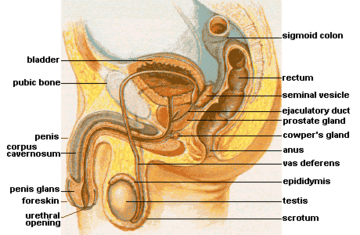

Urinary bladder

Urinary bladder Structure of the penis

Microscopic glands of the prostate Male Anatomy

Male Anatomy The deeper branches of the internal pudendal artery.